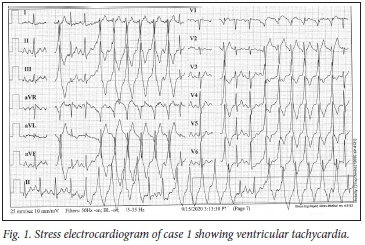

Findings on physical examination were unremarkable apart from the presence of sinus tachycardia of 100 bpm with frequent ectopic beats. Her blood pressure was 135/96 mmHg and her oxygen saturation (sats) 98%. An electrocardiogram (ECG) showed sinus rhythm with multiple ventricular ectopics (Fig. 1). On a multistage treadmill test, there were runs of ventricular tachycardia. Twenty-four-hour Holter monitoring showed frequent ventricular ectopics, bigeminy, couplets and ventricular tachycardia (VT).

The diagnosis was almost certainly the result of a COVID-19 myocarditis that resulted in scarring of the myocardium. A cardiac electrophysiological study identified a number of arrhythmogenic foci in the left ventricular outflow tract from which VT could be induced. These were ablated, and VT could no longer be induced. The patient is now able to exercise safely.

Cardiac complications of COVID-19 include myocardial injury, myocarditis, acute myocardial infarction, heart failure, dysrhythmias, pericarditis and venous thromboembolic events.[1] The prevalence is unclear, but acute myocarditis may account for up to 7% of deaths. It may present with a variety of symptoms including chest pain, dyspnoea, dysrhythmia, and acute left ventricular dysfunction with cardiogenic shock. Serum troponin values are generally abnormal. The ECG can demonstrate a range of findings including nonspecific ST-segment-T-wave abnormalities, T-wave inversion, PR-segment and ST-segment deviations (depression and elevation) and ventricular arrhythmias. The echocardiogram may be helpful in distinguishing pericarditis from acute myocardial infarction. The likely pathophysiology is a combination of the direct viral insult to cardiomyocytes, the immune response to virally infected myocardium, and drugs that prolong the QT interval.[2]

The later cardiac effects of COVID-19 are less well described, and milder cases of myocarditis may go unrecognised and pose potential risks. This possibility understandably leads to caution when advising a return to physical activity after infection. Without evidence from robust studies to inform practice, all current guidance to date is based on consensus or expert opinion.[3] The current consensus is to risk-stratify patients before recommending a return to physical activity. Patients with ongoing symptoms, who had severe COVID-19 or with a history suggestive of cardiac involvement, need further clinical assessment that may include clinical examination, resting and effort ECGs, echocardiography and Holter monitoring, and cardiac magnetic imaging if indicated. In all other cases, after at least 7 days free of symptoms, minimal exertion may be undertaken for 2 weeks before increasing activity.[3] However, case 2 did not meet the criteria for detailed investigations, as a potentially fatal ventricular tachycardia was only detected on Holter monitoring. Perhaps a routine examination and ECG should be advised, as in our case multiple ventricular ectopics were detected that prompted further investigation.